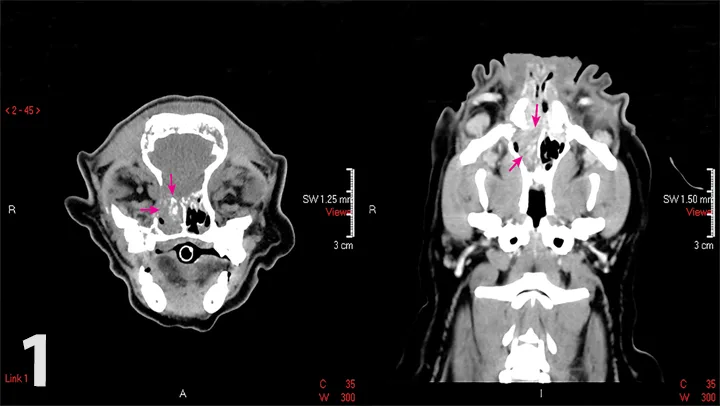

Computed tomography of the skull showed a mass lesion that was causing severe bony lysis of the maxilla, frontal sinuses, nasal turbinates, and cribriform plate, consistent with neoplasia (Figure 1).

Figure 1

Computed tomography scans of the patient’s skull. Note the mass (arrows) in the right nasal passage. Image courtesy of Dr. Paxton Harness